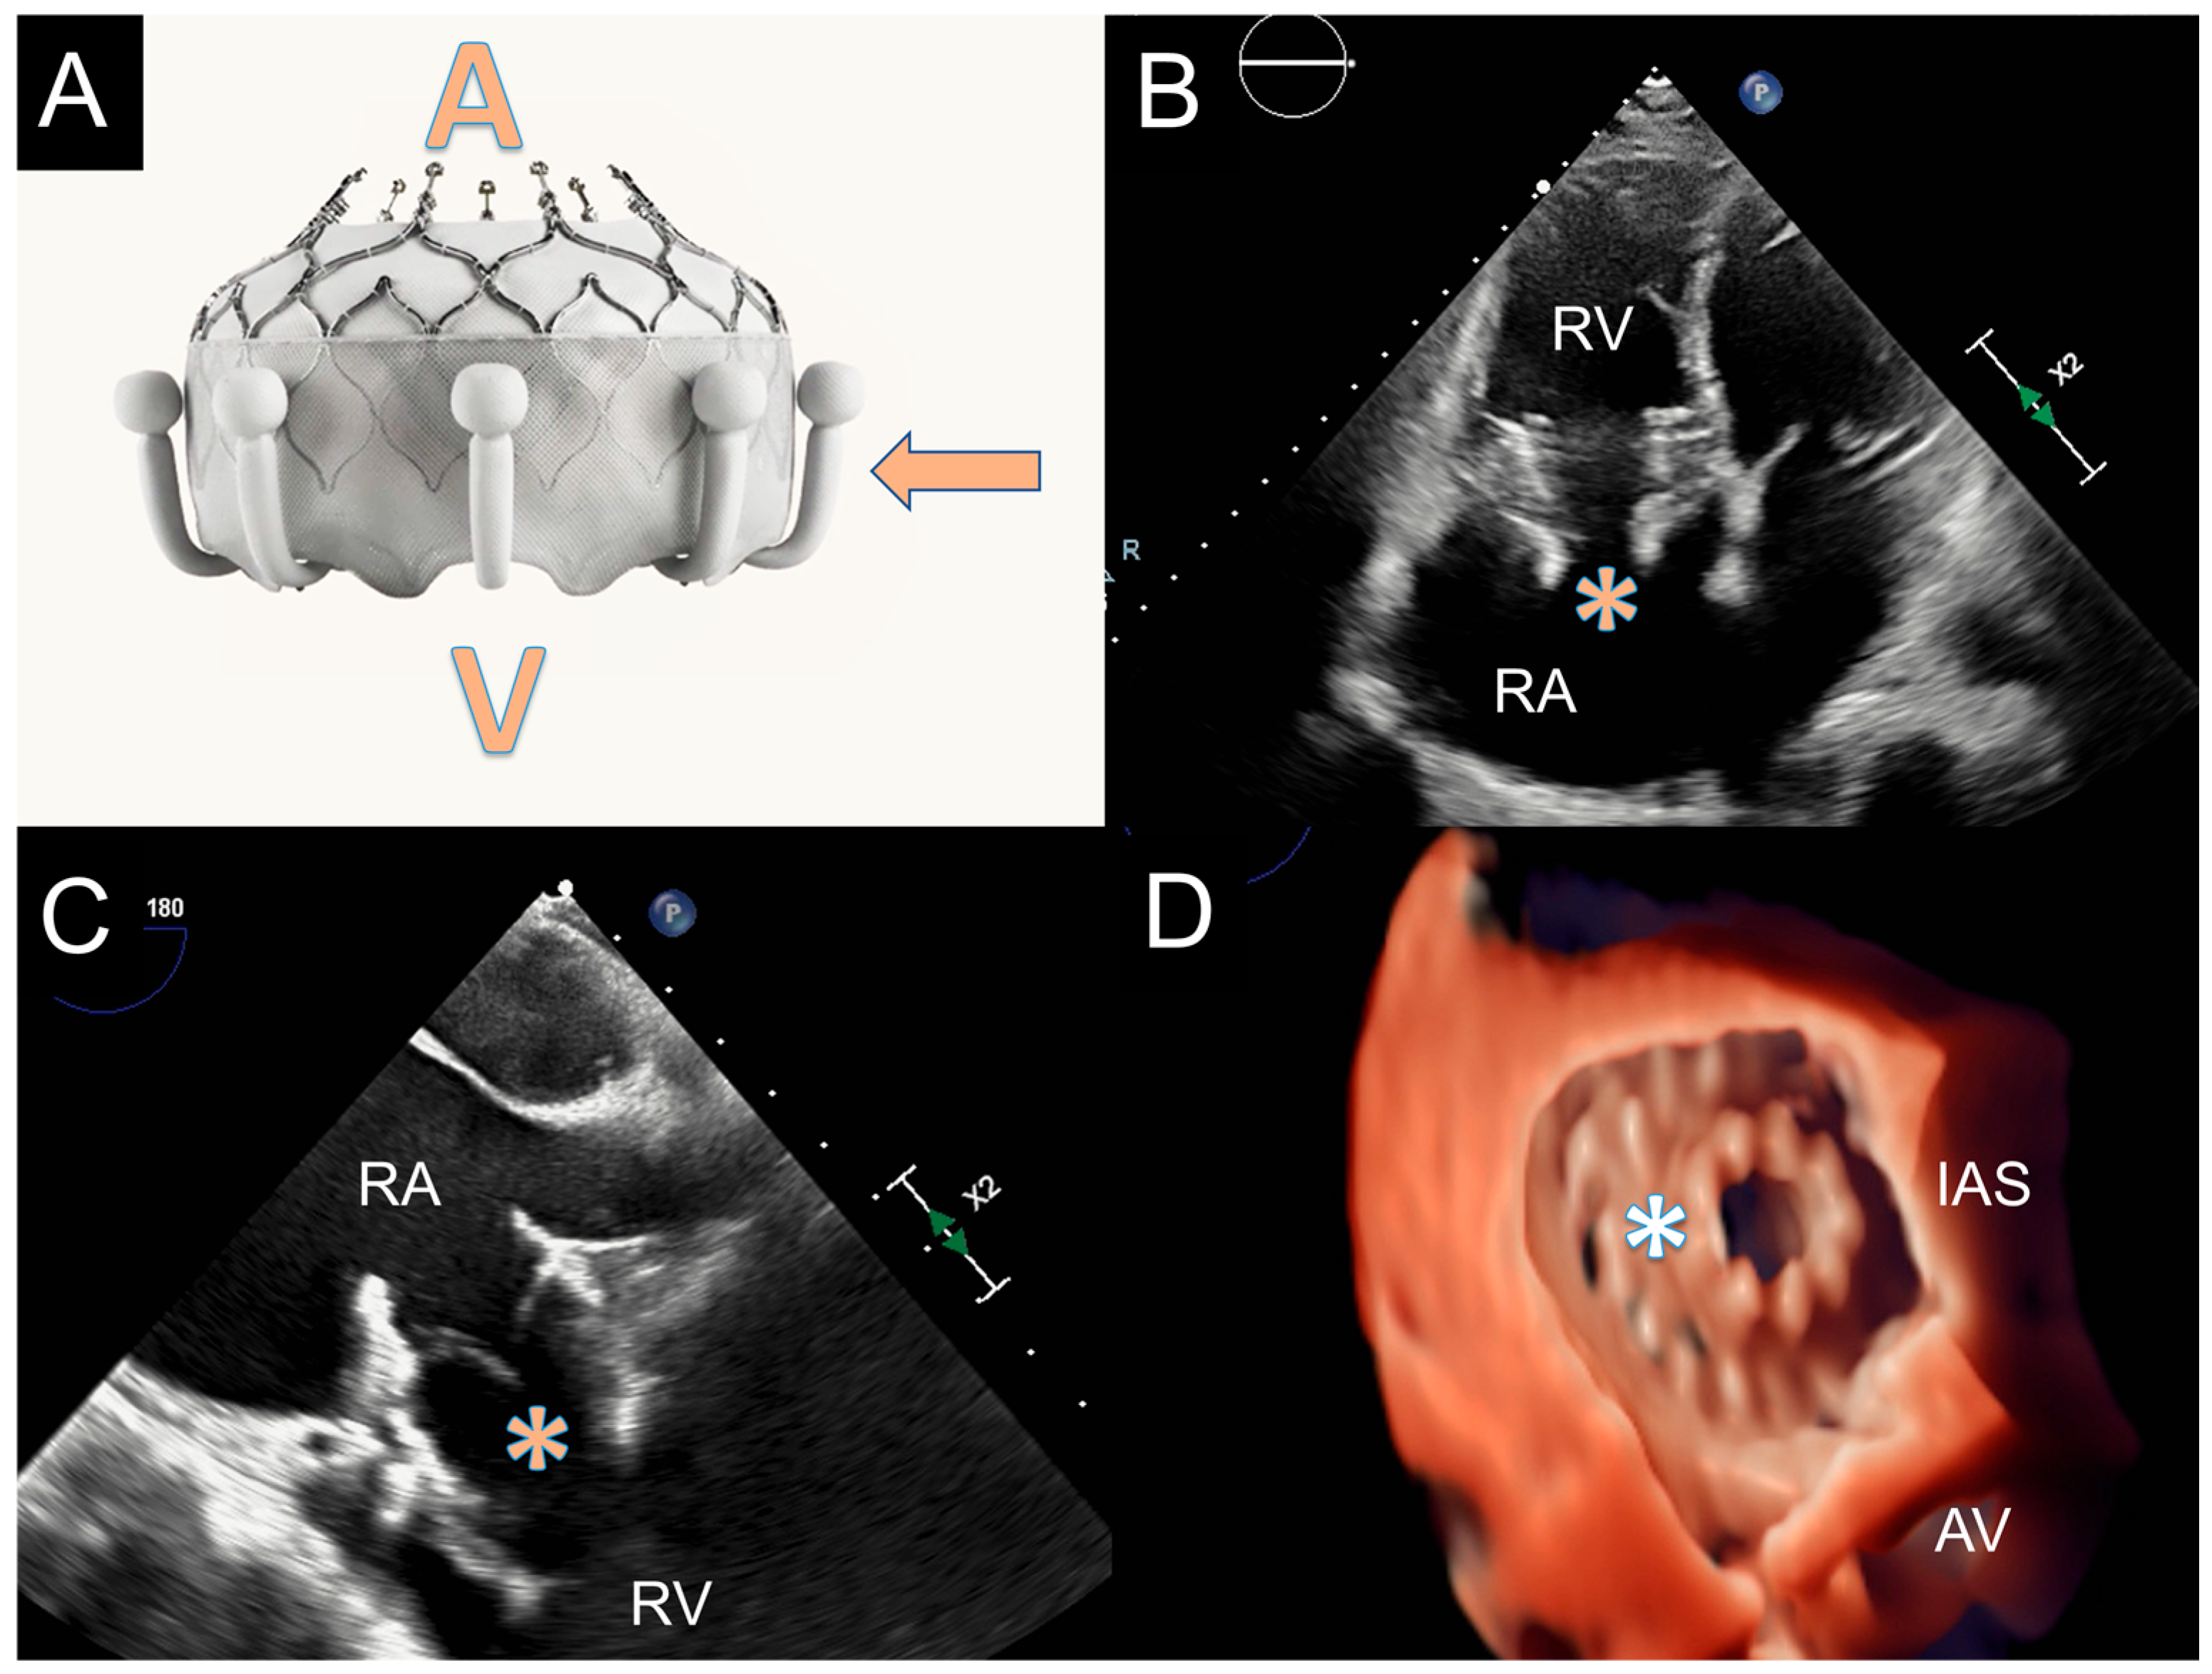

3.2.1. The Evoque System

- TR etiology: classical indications for TTVR are TR patients unsuitable for TEER; thus, in clinical practice, it is very common to see patients with extreme TV anatomies (wide coaptation gap, very large annular dimensions, CIED leads, massive and torrential TR). In the TRISCEND trial, 68.2% of TR were functional (atrial or ventricular forms), 9.7% were primary, 14.2% mixed and 2.8% CIED-related [111]. While atrial functional TR usually do not have challenging anatomies, ventricular forms need to be carefully assessed: annular size can be bigger, and valve leaflets can be characterized by tethering or plastering. High tenting height (>15 mm in systole) or leaflet plastering (a distance between leaflets and RV wall < 4 mm in diastole) can affect leaflets engagement and lead to procedural failure. On the other side, in primary TR due to leaflets prolapse or flail, the excessive leaflets mobility can complicate the procedure. If the prolapse/flail is localized, the case can be considered suitable; in the presence of wide septal prolapse/flail (involving more than a half of the leaflets) or lateral leaflets prolapse/flail (>1/3 of valve circumference) procedural success can be significantly compromised. Rheumatic and carcinoid disease induce valve fibrosis reducing systolic-diastolic leaflets movements; the presence of a completely “frozen valve” in diastole, like it is frequently observed in advanced carcinoid syndrome, can prevent leaflets capture and valve anchoring. In the TRISCEND trial about 3% of patients had CIED leads; after TTVR no leads dysfunction or worse outcomes were observed [111]. The presence of CIED leads is not a contraindication for TTVR. However, a comprehensive analysis of leaflet-lead interaction with multimodality imaging (TTE, TEE, CT) is pivotal [114]. In general, if there is an adhesion of CIED-lead with a leaflet, there may be an interference with Evoque valve deployment, but every case must be analyzed individually to ensure feasibility and to predict adequate procedural results.

- Right chambers size: RA and RV represent the working room of the TTVR procedure; adequate chamber size is needed to manipulate the system and implant the valve. The anatomical working room is generally assessed using a contrast CT scan in diastolic and systolic phases. Using a reformatted 4 chamber view, RA height from the annulus to atrial roof, RV length from the annulus to the apex and the relationship between IVC and TV annulus are assessed [115]. The delivery system must have enough space to orientate and implant the valve without any interference with the surrounding structures. Additionally, CT scan is used to assess the position and the distance of papillary muscles relatively to the annulus: from one side papillary muscles can interfere with valve positioning if they are too close to the valve; from the other side, they can be considered another retention mechanism, thus they can stabilize the ventricular side of the valve after deployment (Figure 8).